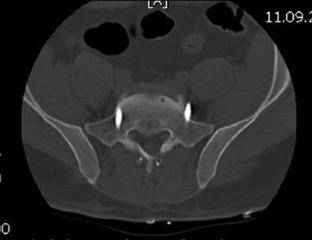

Fig. 1

Fig. 2

Fig. 3

Fig. 4

Fig. 5

Fig. 6

Fig. 7